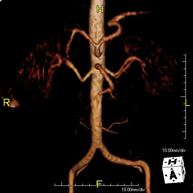

Prova diagnòstica no invasiva que consisteix en l'estudi de l'artèria aorta abdominal i de les artèries ilíaques, amb l'obtenció d'imatges d'alta definició anatòmica mitjançant l'ús d'un camp electromagnètic i ones de ràdio (amb un emissor i un receptor). És indispensable l'ús de contrast paramagnètic (Gadolini). No utilitza radiació ionitzant. La qualitat de les imatges permet realitzar reconstruccions en 2D i 3D. Aquesta prova està especialment indicada com a estudi prequirúrgic (mapa vascular) abans d'intervencions percutànies o quirúrgiques d'aorta abdominal i artèries ilíaques, per a l'estudi complementari en pacients amb isquèmia de membres inferiors, etc. - Angio RM Arterial d'extremitats inferiors

Prova diagnòstica no invasiva que consisteix en l'estudi vascular del sector aorto-ilíac i dels vasos arterials de les dues extremitats inferiors, am l'obtenció d'imatges d'alta definició anatòmica mitjançant l'ús d'un camp electromagnètic i ones de ràdio (amb un emissor i un receptor). És indispensable l'ús de contrast paramagnètic (Gadolini). No obstant, no utilitza radiació ionitzant. La qualitat de les imatges permet realitzar reconstruccions en 2D i 3D. Està especialment indicat en aquells pacients en els que hi ha sospita de malaltia vascular a les dues extremitats, en pacients amb malaltia vascular de les dues extremitats com a mapa vascular abans del tractament (percutani o quirúrgic), com a mapa vascular prequirúrgic en pacients amb lesions òssies o musculars que requereixin cirurgia, etc. - Angio-RM d'Artèries renals

Prova diagnòstica no invasiva que consisteix en l'estudi de l'artèria aorta abdominal per obtenir imatges d'alta definició anatòmica mitjançant l'ús d'un camp electromagnètic i ones de ràdio (amb un emissor i un receptor). És indispensable l'ús de contrast intravenós paramagnètic (Gadolini). No obstant, no utilitza radiació ionitzant. La qualitat de les imatges permet realitzar reconstruccions en 2D i 3D. Aquesta prova està especialment indicada com estudi prequirúrgic (mapa vascular) abans d'intervencions percutànies o quirúrgiques d'aorta abdominal, per a l'estudi complementari en pacients amb isquèmia de membres inferiors, etc. - Angio-RM d'Artèries renals

Prova diagnòstica no invasiva que consisteix en l'estudi de l'artèria aorta abdominal per obtenir imatges d'alta definició anatòmica mitjançant l'ús d'un camp electromagnètic i ones de ràdio (amb un emissor i un receptor). És indispensable l'ús de contrast intravenós paramagnètic (Gadolini). No obstant, no utilitza radiació ionitzant. La qualitat de les imatges permet realitzar reconstruccions en 2D i 3D. Està especialment indicada en pacients amb sospita de malaltia vascular de les dues extremitats, en pacients amb malaltia vascular de les dues extremitats com a mapa vascular abans del tractament (percutani o quirúrgic), com a mapa vascular prequirúrgic en pacients amb lesions òssies o musculars que requereixin cirurgia, etc. - Angio-RM Lesión partes blandas